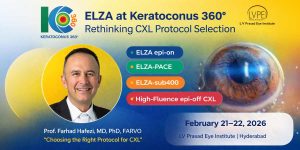

In the 2024 Expertscape rankings, Prof. Farhad Hafezi, MD, PhD, FARVO, is celebrated as the world’s foremost expert – the world’s #1 in CXL.

Current Honors